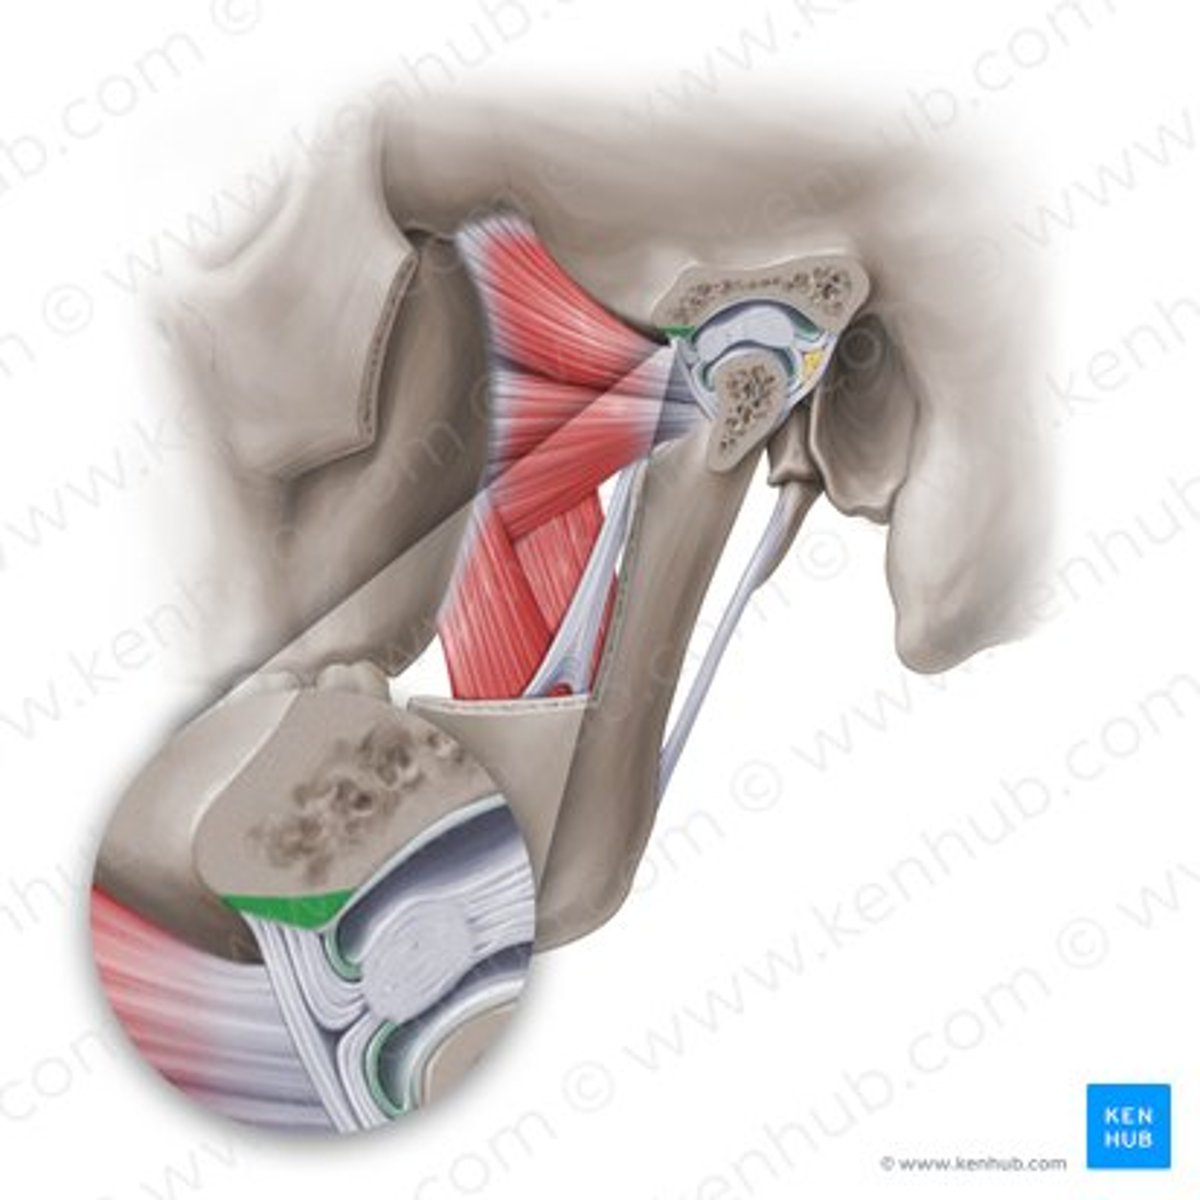

lateral pterygoid, superior part

lateral pterygoid, inferior part

articular tubercle

head of mandible

articular disk

joint capsule